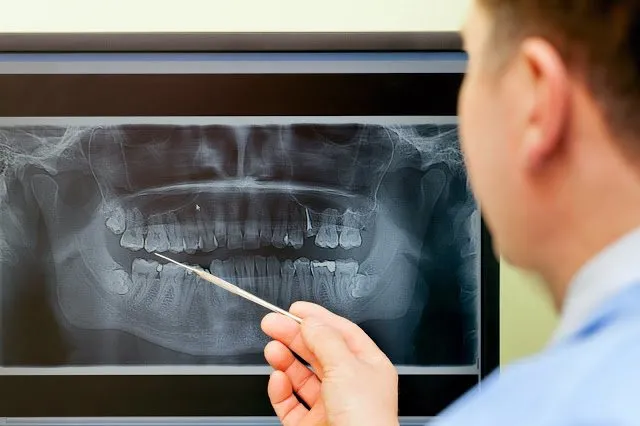

Existem cirurgias que podem ser bem rápidas e outras que podem demorar bastante, isso varia principalmente pela posição do dente.Por isso é essencial exames complementares como a panorâmica.

Além disso, existem casos mais complicados que necessitamos realizar uma tomografia. Nesses exames vamos examinar primeiramente a posição do siso, ele pode estar na posição "normal" ou em "pé", ou seja,como todo outro dente.

Portanto, existem casos mais simples e outros mais complexos que devemos planejar com bastante cuidado.